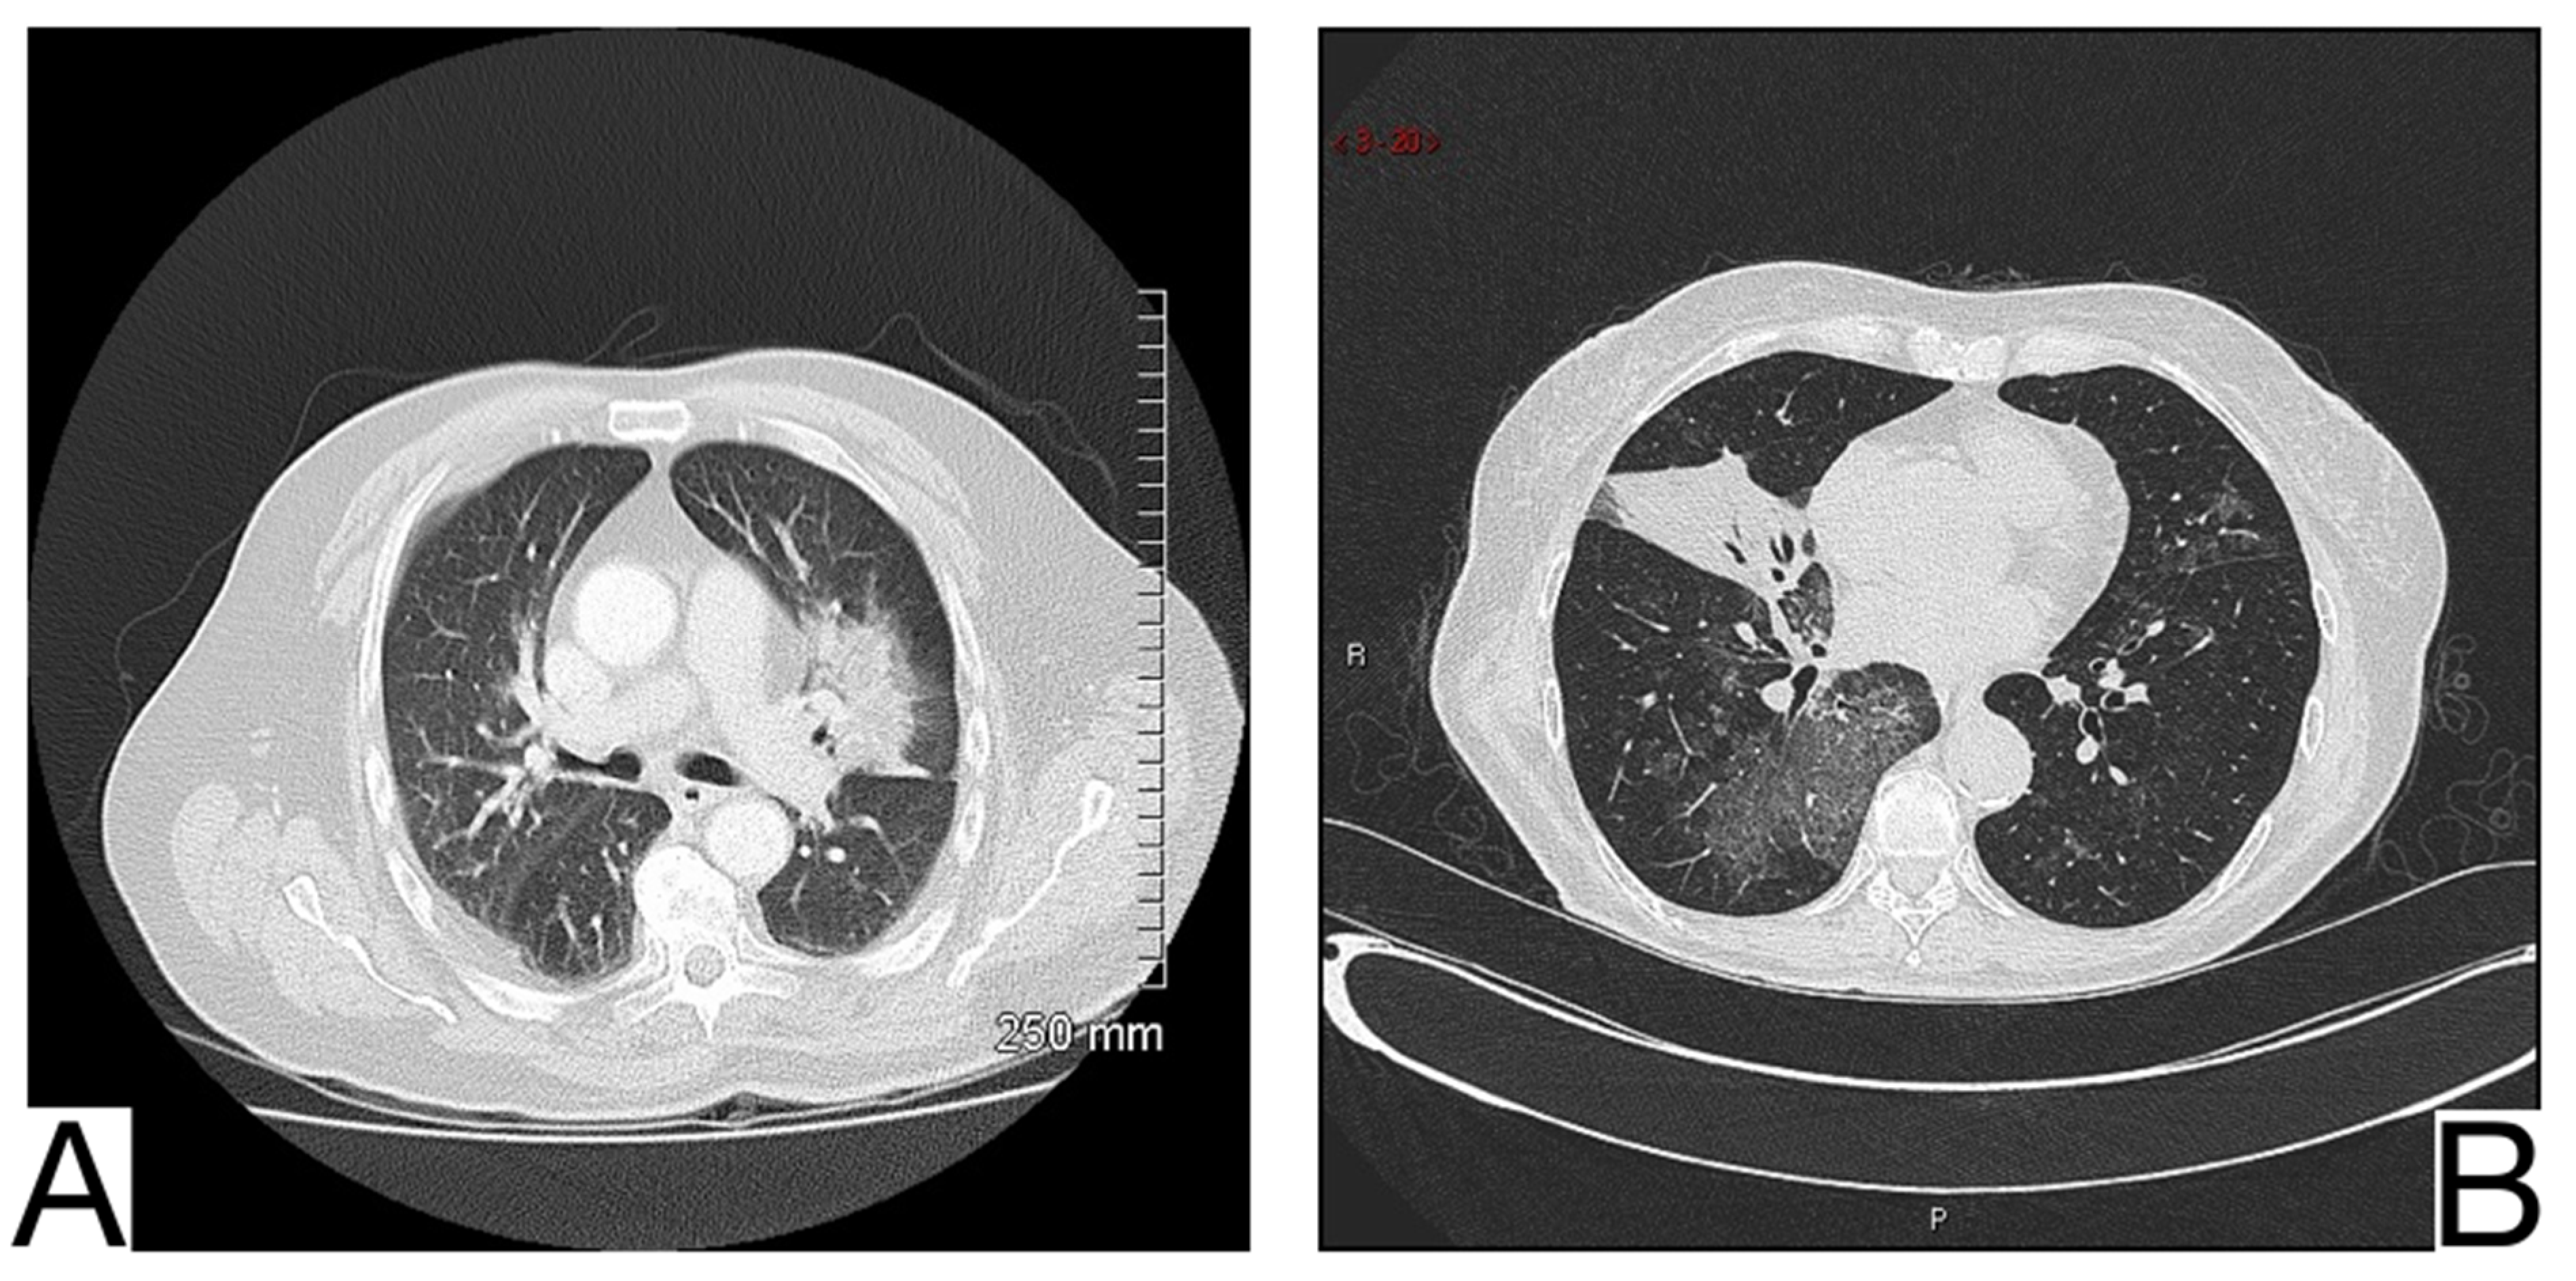

10.4. Aspergillosis

10.5. Cardiovascular Pathologies

10.5.1. Acute Pulmonary Edema